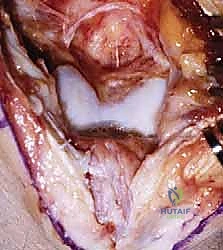

مع مرور الوقت وسنوات من الإجهاد المتكرر، يمكن أن تتآكل الغضاريف الملساء التي تغطي أسطح المفصل وتعمل كوسادة ممتصة للصدمات. هذا التآكل يؤدي إلى احتكاك العظام ببعضها البعض بشكل مباشر. كرد فعل دفاعي (ولكنه ضار في هذه الحالة)، يقوم الجسم بتكوين نتوءات عظمية (Osteophytes) حول حواف المفصل في محاولة لزيادة مساحة السطح وتقليل الضغط.

هذه النتوءات هي السبب الرئيسي للألم وتحديد الحركة؛ حيث تصطدم ببعضها البعض (Impingement) أو تحتك بالعظام المقابلة عند محاولة تحريك الكوع. كما يمكن أن تنفصل أجزاء صغيرة من هذه النتوءات أو الغضاريف المتآكلة لتتكون "أجسام حرة" (Loose Bodies) تسبح داخل السائل المفصلي، وهي قطع صغيرة يمكن أن تنحشر بين أسطح المفصل مسببة ألماً مفاجئاً حاداً، طقطقة مسموعة، أو قفلاً كاملاً للمفصل (Joint Locking).

- المفصل الزندي العضدي (Ulnohumeral Joint): هذا هو المفصل الأساسي الذي يسمح بحركتي الثني (Flexion) والمد (Extension). يتكون من التقاء بكرة العضد (Trochlea of the Humerus) مع الشق الزندي الأكبر (Greater Sigmoid Notch of the Ulna). وهو محور اهتمامنا الرئيسي في جراحة أوتبيردج-كاشيواجي، حيث تتكون معظم النتوءات العظمية المعيقة للحركة.

في حالات خشونة الكوع، تمتلئ هذه الحفر بالنتوءات العظمية والأنسجة الليفية، مما يمنع العظام من الدخول في أماكنها الطبيعية، وهذا هو التفسير الميكانيكي لعدم قدرة المريض على فرد أو ثني ذراعه بالكامل.

سُميت هذه العملية تيمناً بالجراحين اللذين قاما بتطويرها. تعتمد الفكرة الأساسية لهذه الجراحة العبقرية على مبدأ ميكانيكي بسيط ولكنه فعال للغاية. في الكوع المتيبس بسبب الخشونة، تتكون نتوءات عظمية في الجزء الأمامي (الناتئ الإكليلي والحفرة الإكليلية) والجزء الخلفي (الناتئ الزجي والحفرة الزجية).

بدلاً من إجراء شق جراحي أمامي وشق جراحي خلفي كبيرين للوصول إلى هذه النتوءات، يتم الوصول إلى المفصل من الخلف فقط. يقوم الدكتور هطيف بإزالة النتوءات العظمية الخلفية، ثم يقوم بـ إحداث ثقب (Fenestration) أو نافذة دقيقة في العظم الرقيق الفاصل بين الحفرة الزجية (الخلفية) والحفرة الإكليلية (الأمامية) لعظمة العضد.